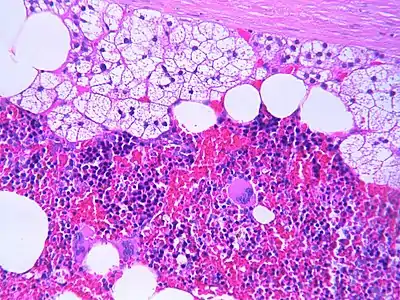

The microscopic view of a myelolipoma shows the presence of normal adrenal cells, fat (adipose) cells, and the three lineages of the myeloid precursors

The typical microscopic features of myelolipomas are shown in the image. There is a mixture of normal adrenal tissue, fat, and a full trilineage maturation of the three major blood-forming elements: myeloid (white blood cell forming), erythroid (red blood cell forming), and megakaryocytic (platelet forming) lines.[1]